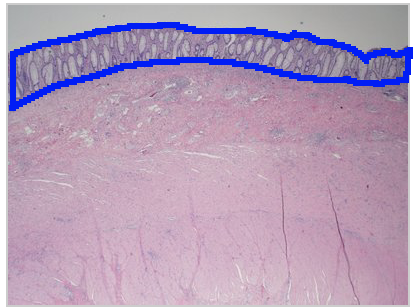

In this image, identify the columnar epithelium.

The shapes and dimensions of epithelial cells are quite variable, ranging from columnar, cuboidal to low squamous cells. In this image, the columnar epithelium is characterized by the cells being taller than they are wide, and the nuclei are basally located.